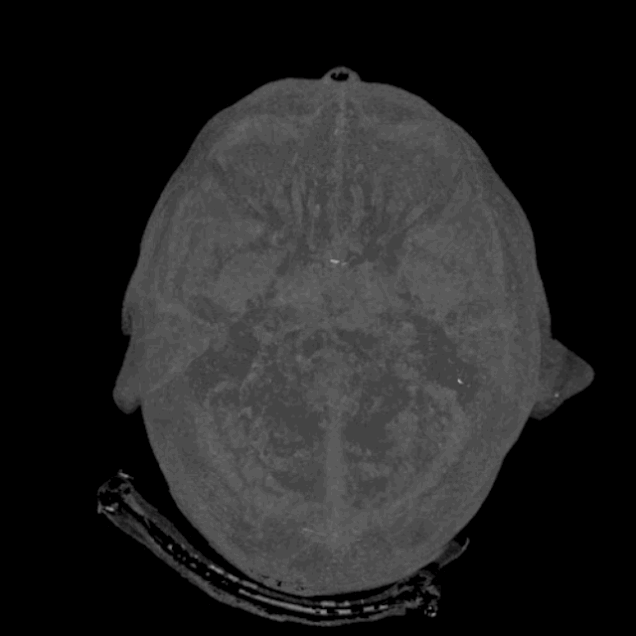

BigBrain

BigBrain es una reconstrucción digital del cerebro humano completo en 3D y ultra-alta resolución, que deja muy atrás a cualquier iniciativa anterior de este estilo. Es la herramienta esencial que necesitan los laboratorios neurológicos de todo el mundo para elucidar la forma y la función de nuestro cerebro. Y estará disponible públicamente a coste cero.

Hasta ahora existen otros atlas del cerebro, pero solo llegan al nivel macroscópico, o visible. Su resolución solo llega al nivel de un milímetro cúbico, y en ese volumen de cerebro caben fácilmente unas 1.000 neuronas. El nuevo BigBrain baja el foco hasta un nivel “casi celular”, según los científicos que lo han creado. Eso quiere decir que llega a discriminar cada pequeño circuito de neuronas que está detrás de nuestra actividad mental, y que puede abarcar toda la información disponible sobre el cerebro, desde los genes y los receptores de neurotransmisores hasta la cognición y el comportamiento.

Pese a que hay cientos de laboratorios en el mundo investigando en neurobiología, el cerebro no contaba hasta ahora con una gran planificación de este tipo, como las que se usan para secuenciar el genoma humano o encontrar el bosón de Higgs. La gran ciencia ha llegado al cerebro, y BigBrain permite por primera vez una exploración en 3D de la anatomía citoarquitectónica humana.

BigBrain, ya forma parte del dominio público, y es un gran paso hacia el entendimiento profundo del cerebro y la mente. Su objetivo no es otro que comprender los fundamentos neurobiológicos del aprendizaje y la adquisición de conocimiento, del lenguaje y las emociones, de la torpeza y de la creatividad humana. El trabajo ha sido coordinado por Katrin Amunts, del Instituto de Neurociencia y Medicina de Jülich, en Alemania; y Alan Evans del Instituto Neurológico de la Universidad McGill en Montreal, Canadá.

El cerebro de referencia se basa en el de una mujer fallecida a los 65 años, que ha sido fileteado en 7.400 secciones histológicas de solo 20 micras (el espesor de un cabello, y cerca de la dimensión de una célula). El BigBrain, según sus creadores, abre el camino para entender las bases neurobiológicas de la cognición, el lenguaje y las emociones, y también para investigar las enfermedades neurológicas y desarrollar fármacos contra ellas.[3]